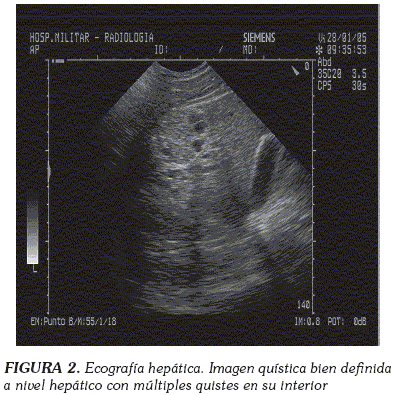

Se realizó una biopsia pleural en la que se observaron abundantes eosinófilos y linfocitos sin granulomas; una ecografía hepática que evidenció en el hígado una imagen quística bien definida con quistes en su interior (Figura 2); una tomografía computarizada toraco-abdominal que mostró, en varios cortes, múltiples quistes de densidad heterogénea compatibles con hidatidosis (Figura 3) y una resonancia nuclear magnética en la que se visualizó un área quística en la zona 6 hepática, sin descartar solución de continuidad en diafragma (Figura 4). Finalmente se realizó una serología para Echinococcus spp. que resultó positiva.

Ultrasonido: Es el procedimiento diagnóstico de elección para casos hepáticos, aunque pueden existir hasta un 10% de falsos positivos debido a la presencia de quistes serosos, abscesos o tumores. Las principales características de la enfermedad hidatídica incluyen la demostración de septos dentro del quiste y la formación de quistes hijos (66). La ecocardiografía, por otra parte, se ha utilizado también en la evaluación radiológica de quistes cardiacos (67).